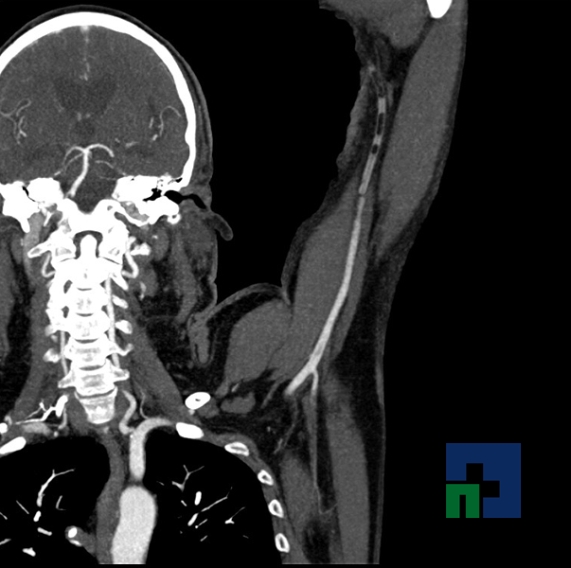

Examinare de rutină cerebrală, nativ și cu substanță de contrast (SDC) pentru diagnosticul:

- Accidentelor vasculare cerebrale ischemice sau hemoragice

- Fistula carotido-cavernoasa